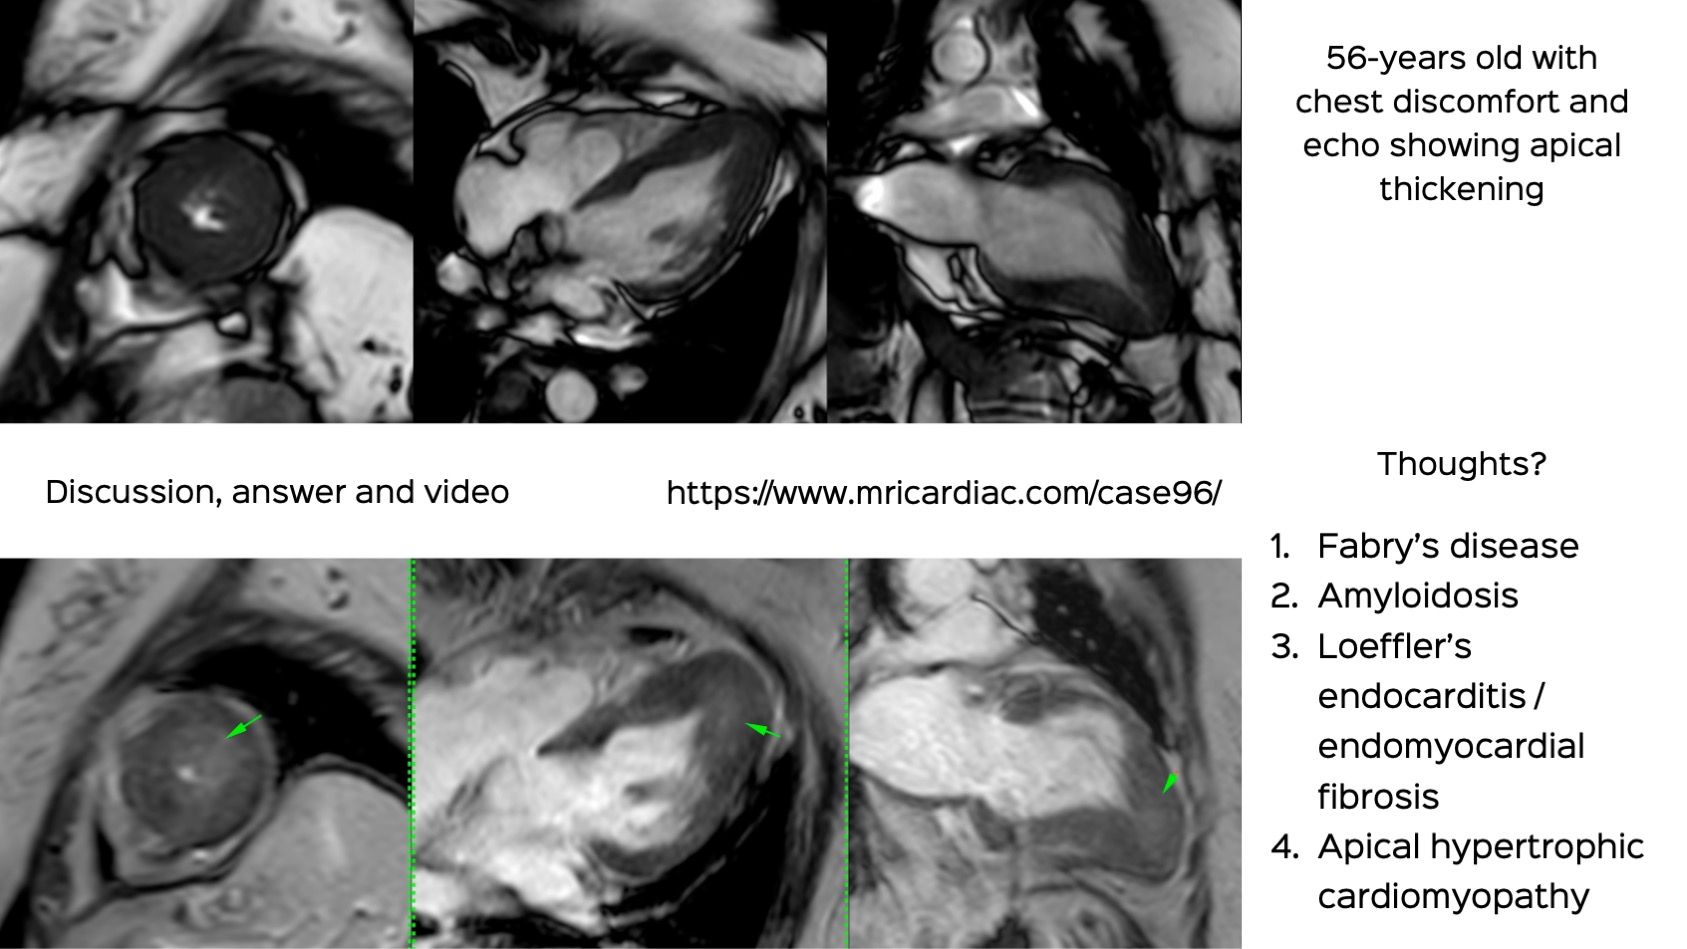

Case 96: The Ace of Spades

This is a 56-years old who presented with chest discomfort and echo showed apical thickening.

What do you think is the diagnosis?

- Fabry's

- Amyloidosis

- EMF

- Apical hypertrophic cardiomyopathy